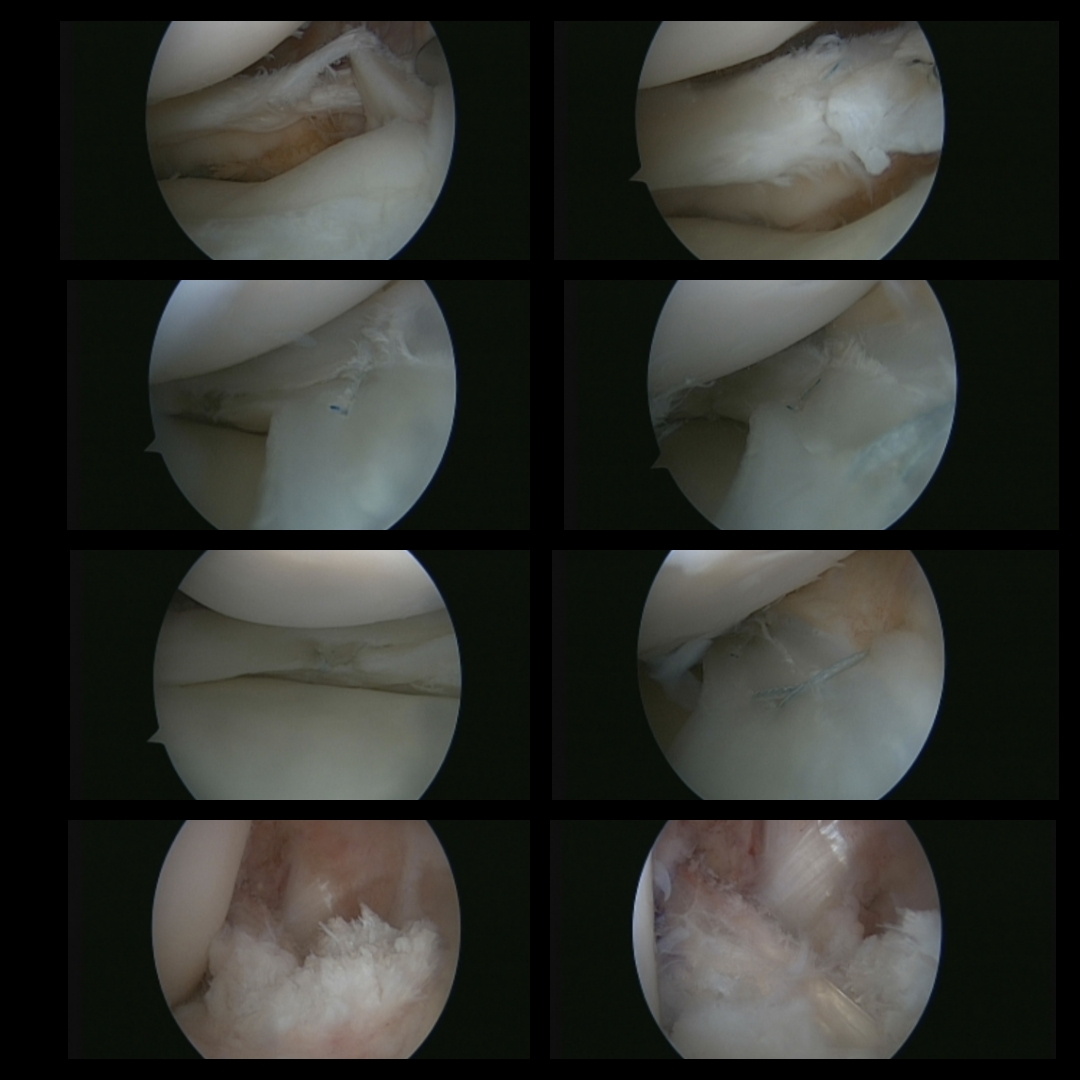

Read MoreHistory: 17-yr-old boy suffered from a bucket handle tear of the Medial Meniscus, complex tear of Lateral Meniscus and ACL Tear. Case: A medial meniscus Repair of the bucket handle with all inside, Inside out and Outside in technique was…